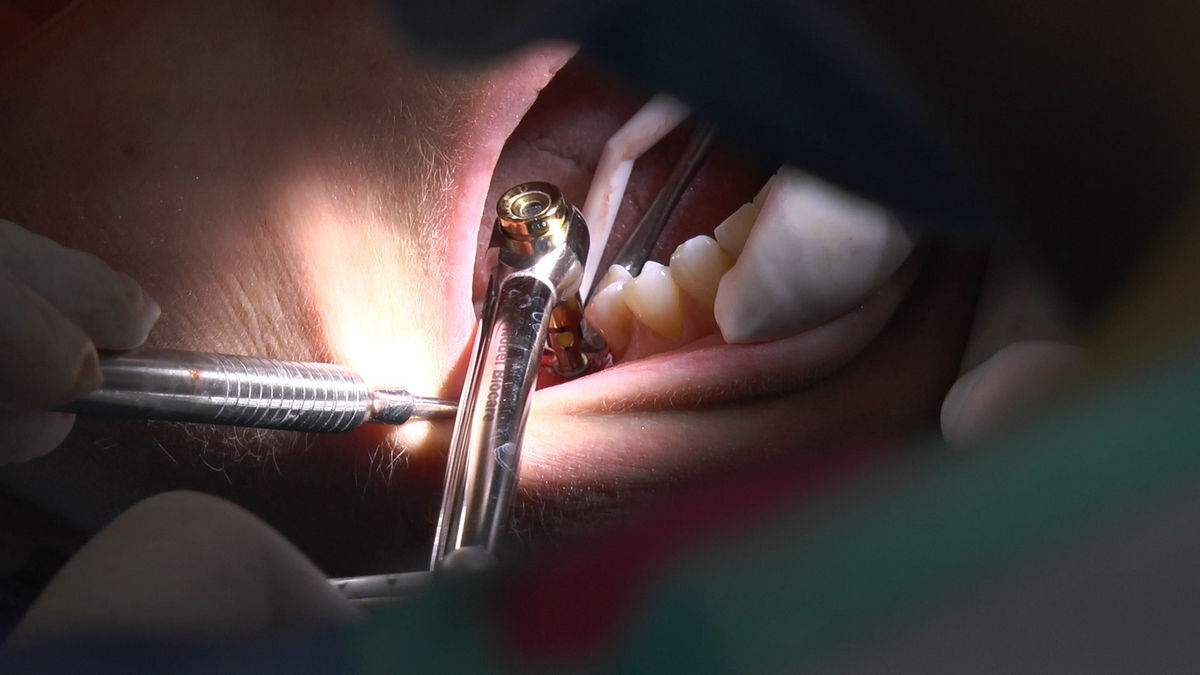

Practiculum Implantologii – Sezon V/B, sesja 8, część 4